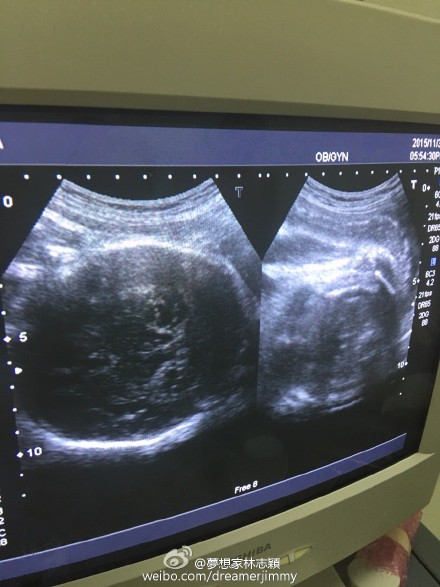

11月30日晚,林志穎通過微博曬出老婆的B超照,并給大家報平安,寫道:“陪老婆產(chǎn)檢,baby很健康!”

新浪娛樂訊 11月30日晚,林志穎通過微博曬出老婆的B超照,并給大家報平安,寫道:“陪老婆產(chǎn)檢,baby很健康!”此微博曝光后,網(wǎng)友紛紛留言囑咐要好好照顧老婆和兒子。

早前,林志穎為了慶祝微博粉絲破六千萬,公布妻子懷孕喜訊,并透露是雙胞胎,預產(chǎn)期是在12月,會在臺灣剖腹生產(chǎn)。近日,林志穎在微博曬快餐店的自拍照,透露是為孕妻買夜宵,并稱老婆特別能吃。(我是彌爾)